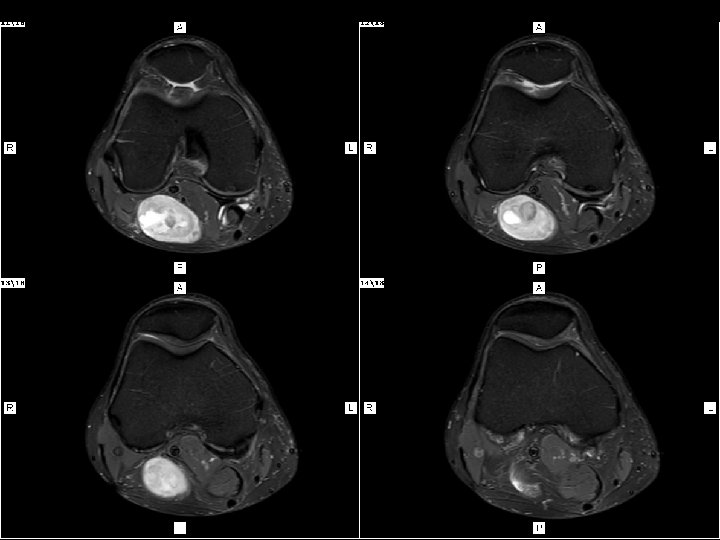

Hombre de 57 años de edad Tumoración y dolor tipo eléctrico desde el hueco poplíteo hasta la planta del pie de 2 años de Evolución. Niega antecedente traumático Solicitan RM de Rodilla Derecha con diagnóstico presuntivo de QUISTE DE BAKER y trae ecografía Previa

AXIAL SAGITAL PANORAMIC VIEW (PW) HUECO POPLITEO DERECHO - SUPERIOR

¿Diagnósticos diferenciales? • Tumor benigno de la vaina del nervio – Schwnnoma, Neurofibroma • Tumor maligno de la vaina del nervio (bordesinfiltrativo-tamaño) • Aneurisma trombosado • Hematoma • Quiste sinovial complicado

Quiste Baker Lesión en intima relación estructura nerviosa

Nervio peroneo comun Nervio tibial Lesión en intima relación estructura nerviosa Quiste Baker

NEUROFIBROMA – SCHWANNOMA ¿? Definición : TUMOR BENIGNO DE LA VAINA DE NERVIO PERIFERICO Señal: HETEROGENEA CON AREAS DE DEGENERACION QUISTICA Ubicación : INTIMA RELACION CON NERVIO